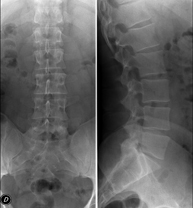

Técnica mediante la cual, utilizando rayos X, se obtienen imágenes del abdomen (estómago, intestino delgado, intestino grueso, hígado, riñones, vejiga, pelvis ósea, etc.) para su estudio. - RX Columna lumbar

Técnica mediante la cual, utilizando rayos X, se obtienen imágenes de la columna lumbar para su estudio. - TEGD (Tránsito Esófago – Gastro – Duodenal)

Técnica mediante la cual, utilizando rayos X, se obtienen imágenes de la columna dorsal para su estudio. Indicaciones: traumatismo, dolor de espalda. - RX Columna lumbar

Técnica mediante la cual, utilizando rayos X, se obtienen imágenes de la columna lumbar para su estudio. Indicaciones: ciática, traumatismo, dolor lumbar. - RX Sacro-cóccix